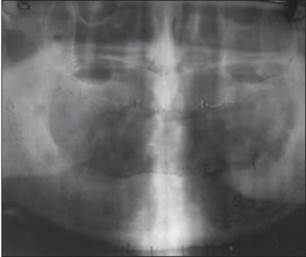

Un paciente de sexo masculino de 58 años había acudido al ala de pacientes externos de nuestro departamento, con una queja principal de falta de diente en los arcos maxilar y mandibular. El paciente quiere tener una prótesis fija ya que no estaba contento con la dentadura convencional [Figura 1] y [Figura 2] . Se registró un historial de casos adecuado para el paciente, incluido un historial médico que no era contributivo, con pruebas de laboratorio relevantes, exámenes dentales y orales. Se prepararon impresiones de diagnóstico y moldes. Se realizó un examen exhaustivo y el paciente estaba motivado para implantar prótesis. El mapeo óseo se realizó para evaluar el ancho del hueso, mediante el uso de ortopantamografía (OPG), se calculó la longitud del hueso disponible y se seleccionaron los implantes de tamaño apropiado [Figura 3]. Se preparó una plantilla quirúrgica para el maxilar y la mandíbula, y la posición de los implantes se decidió antes de la cirugía colocando un taladro en el implante.

Figura 3: Mapeo óseo y radiografía preoperatoria |